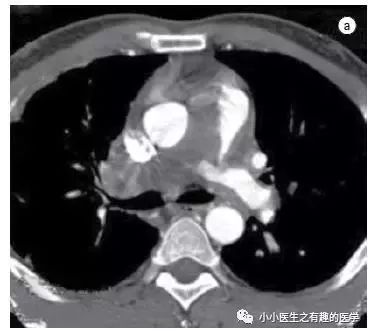

足球王国巴西报道的一例。

这是什么?

病理:Intimal sarcoma of the pulmonary artery,肺动脉内膜肉瘤。

仔细看看:

CT示肺动脉内肿块,肿块侵犯纵隔,血栓不会跑到纵隔。